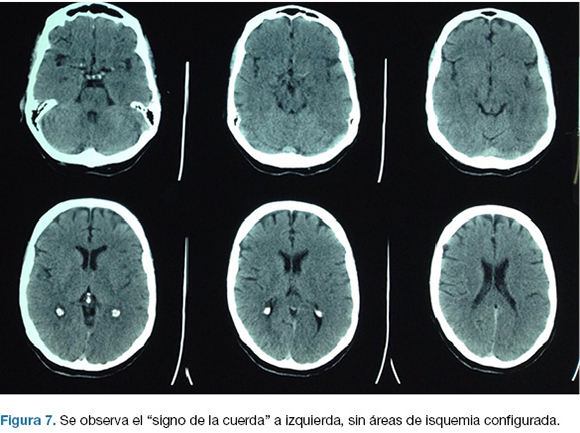

Hombre, 58 años. Con antecedentes personales de HTA, fumador, portador de enfermedad pulmonar obstructiva crónica (EPOC). 2 horas previas al ingreso instala de forma brusca síndrome hemisférico izquierdo. Al ingreso se destaca paciente vigil, afasia, hemiplejia derecha. CGS: 12. NIHSS: 24.

Se realiza TC de cráneo (Figura 7) y rTPA i/v. Ingresa a la unidad de ACV y a las 30 horas del inicio de los síntomas en forma brusca deprime conciencia e instala anisocoria a izquierda. Nueva TC de cráneo (Figura 8), surgiendo la indicación de intervención de emergencia.